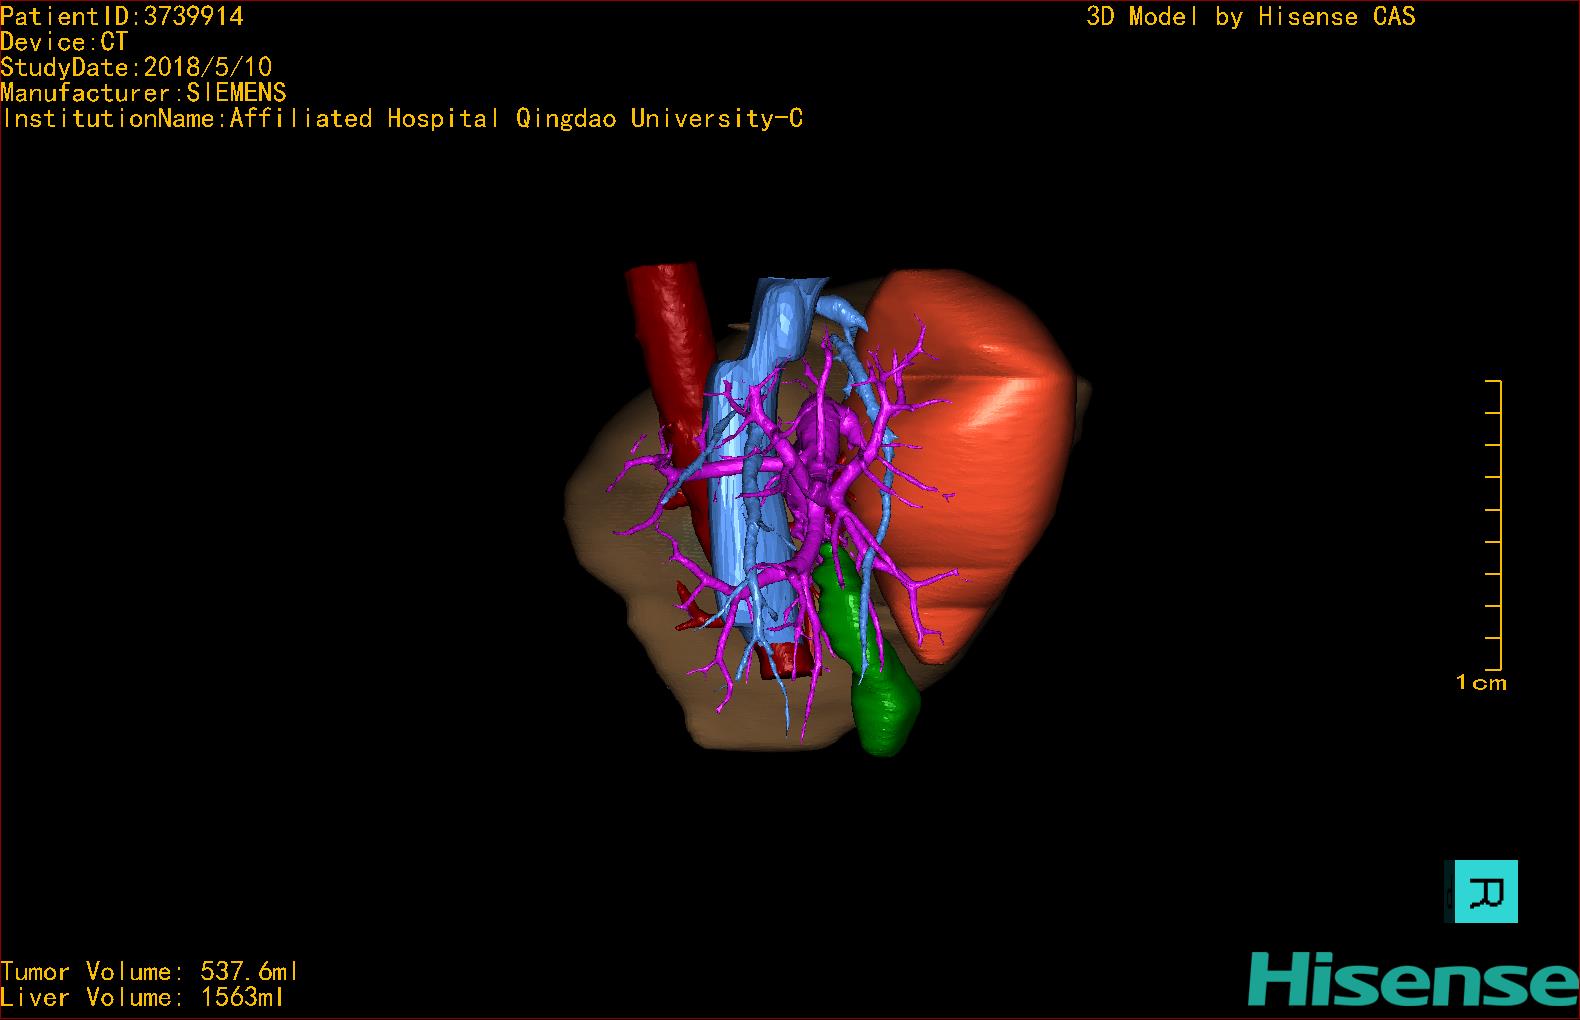

实验室检查: 血常规:WBC 4.89*109/L,RBC 3.64*1012/L, HB 119.00g/L, HCT 35.40%,PLT 123*109/L,RET% 0.48%, RET 0.017*1012/L, IRF 2.00%生化全套:ALT 56.00U/L AST 60.00U/L, LDH 312.00U/L TP 72.08g/L ALB 32.44g/L, GGT 101.00U/L,TBA 21.90umol/L,A/G 0.82,ADA 23.00U/L, PAB 94.20mg/L, CHE 5405.00U/L 肿瘤标志物:CEA 2.80ng/mL CA19-9 11.46U/ml 肝炎全套: HAV-IgM 0.21S/CO, HBcIgM 0.330S/CO, HCV-cAg 0.08S/CO, HEV-IgM 0.03S/CO, HBeAg 6.000S/CO 诊疗过程: CT结果输入海信CAS系统后行3D重建及手术规划后,于2018-5-17局麻下行“经皮肝动脉造影术+肝动脉化疗栓塞术”手术治疗 术前三维重建及手术方案设计: 将0.625mm双源薄层CT资料的静脉期和动脉期Dicom格式文件导入海信CAS系统。 通过调节窗宽窗位调整CT序号,对肿瘤,肝实质,胆囊,下腔静脉,肿瘤,肝动脉、门静脉及肝静脉等进行三维重建;系统自动计算肿瘤体积和肝脏体积。肝脏体积为1563ml,肿瘤体积为537.6ml,通过比对50-60岁正常肝脏体积为1343.28±246.69ml。 手术步骤: 常规准备后,患者仰卧于DSA手术床。常规双侧股动脉区域消毒,铺巾。2%利多卡因局部麻醉右侧股动脉区成功后,应用Seldinger技术穿刺右侧股动脉,置入5F动脉鞘。送5F 肝导管至腹腔干、肝动脉造影,肝区可见团块状及多发结节状肿瘤染色、侵犯门静脉左支。静脉推注维瑞特5mg后,透视下将微导管分别超选择至各支肿瘤供血动脉内,应用雷替曲塞4mg+奥沙利铂50mg+表柔比星20mg +LP 10ml的混合液及适量350-560um明胶海绵进行栓塞,后造影示栓塞适量,退出导管、血管鞘,局部压迫10min,加压包扎。患者术中未诉不适,术后平车安返病房。随访情况: 患者术后3月复查上腹CT示肝左叶病变活性残留,腹腔内、腹膜后多发略大淋巴结,部分较前略减小,今患者为求进一步诊治,与我院再次行“肝动脉造影+经导管肝动脉栓塞术”,术后2周无明显不适 术前CT检查:动脉期

术前三维重建:重建图片.jpg)